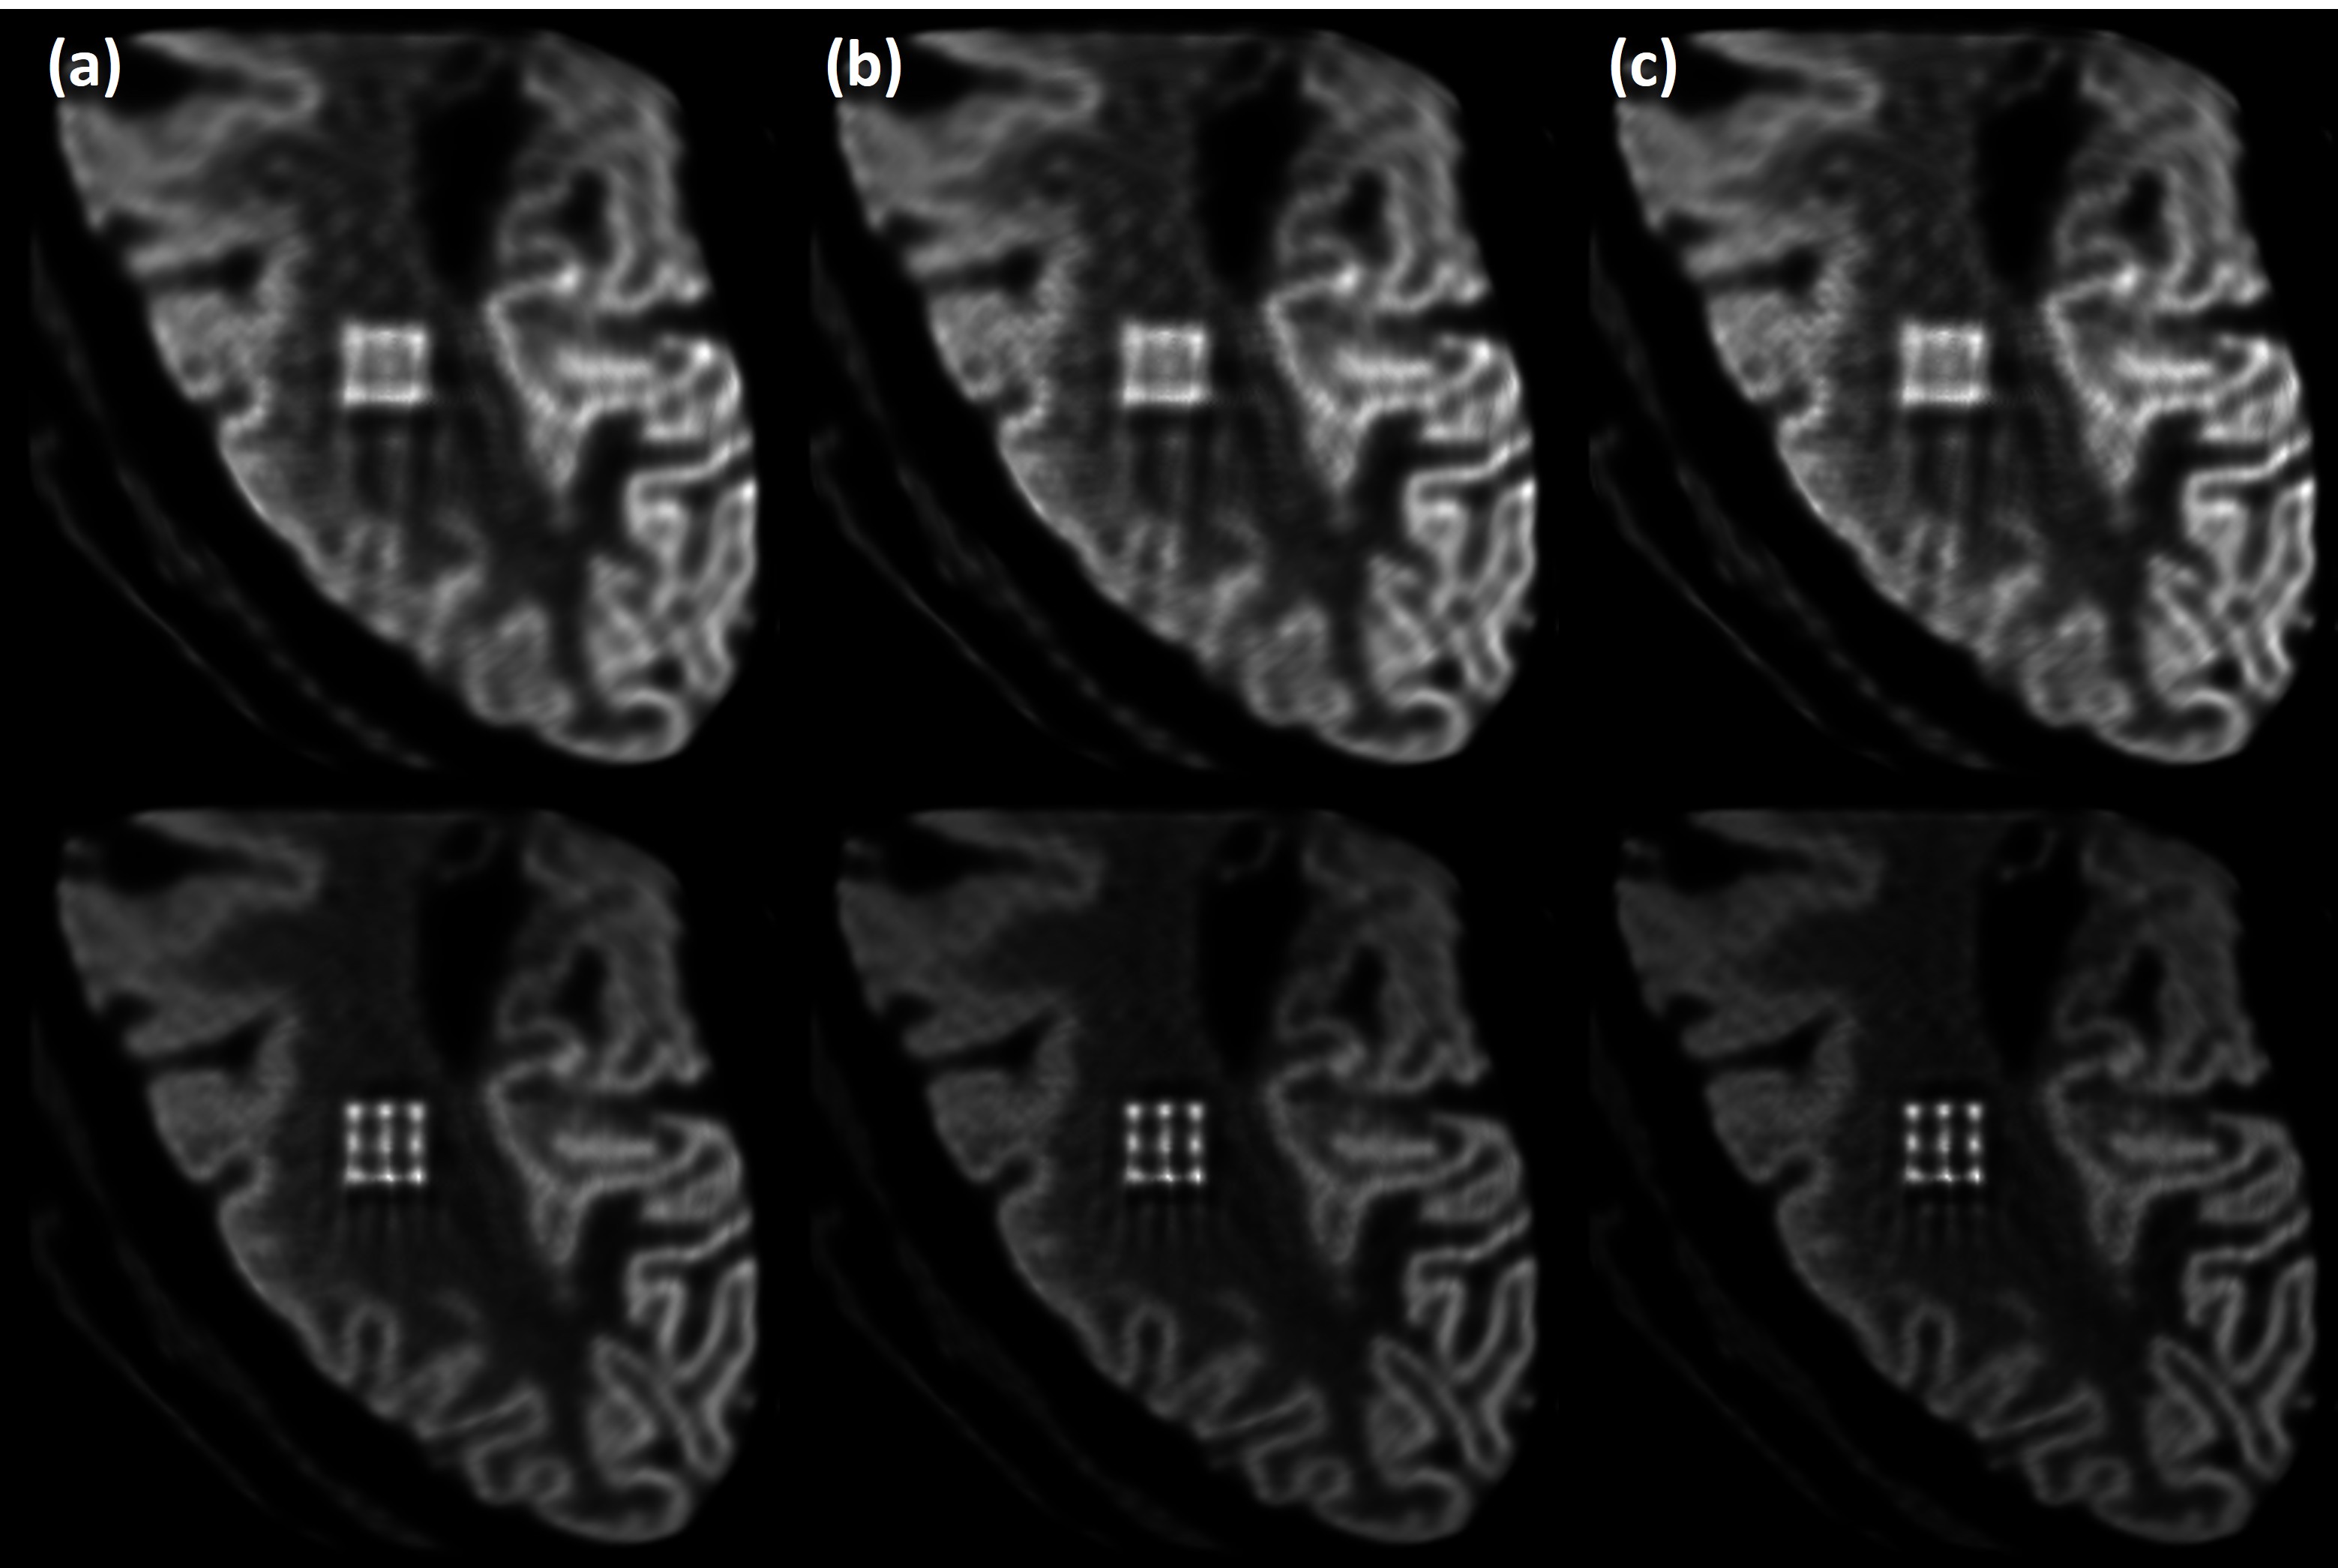

Figure 12: Noise-free images obtained for the brain phantom by M0 (top) and M2 (bottom), using 50 (a), 100 (b), and 200 (c) OSEM iterations. Analytical methods were used for data generation and image reconstruction.

Fig. 12 shows noise-free M0 (top row) and M2 (bottom row) images obtained for the brain phantom by using various number of iterations when using analytically calculated forward and backward projectors for data generation and image reconstruction. The phantom was placed at the center of the system, and 5 mm thickness tungsten was assumed for M2. At the same number of iterations, M2 has better resolution than M0. The M2 image can clearly distinguish the positions and boundaries of 9 lesions, while the M0 image fails to resolve them. Additionally, the M2 image also shows better definition of the gray matter gyri.

Figure 13: Noisy images obtained for the brain phantom by M0 (top) and M2 (bottom), using 20 (a), 50 (b), and 100 (c) OSEM iterations when adding Poisson noise to the analytically simulated data. The M0 and M2 data had 8.0M and 4.6M events respectively, corresponding the same scan duration.

Fig. 13 shows the resulting M0 and M2 brain-phantom images when Poisson noise was added to the above analytically simulated data. An identical scan duration was considered, producing 8.0M and 4.6M events for M0 and M2, respectively. As more iterations are used, for both M0 and M2 images the resolution improves but noise also increases. At the same number of iterations, M2 consistently shows better resolution than M0. Specifically, the M2 image can resolve the lesions at 50 iterations but M0 does not, even at 100 iterations. Arguably, at 100 iterations many structures in M2 are obscured by noise.